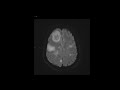

Lymphoma

54 year old woman who presented with progressive left sided weakness and left facial droop. Imaging demonstrates multiple T2 hypointense, enhancing lesions which demonstrate restricted diffusion compatible with hypercellularity. Findings are most compatible with CNS lymphoma with the T2 hypointensity being particularly characteristic of this lesion. Predisposing factors include a history of HIV, EBV infection, or post transplant status (PTLD). The majority are iso to hypointense on T2, enhancement and diffusion restriction is variable. If low grade, surgery may be effective. Otherwise, treatment is with steroids and chemotherapy with or without radiation. The differential for this appearance includes metastasis.